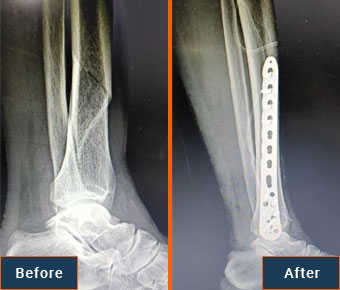

Dr. Amit Singh is an eminent Orthopaedic and Joint Replacement Surgeon in Mumbai. He has done MBBS and MS in Orthopaedics from the reputed Lokmanya Tilak Medical College and General Hospital (Sion Hospital). He has done a fellowship in Primary and Revision Hip and Knee Arthroplasty from South Korea. Dr. Amit Singh focuses on providing integrated orthopedic care at affordable prices to his patients. He always tries to make the pt understand the disease process, and how he can prevent himself from further complications and helps in selecting the best treatment option. He and his team are easily approachable.